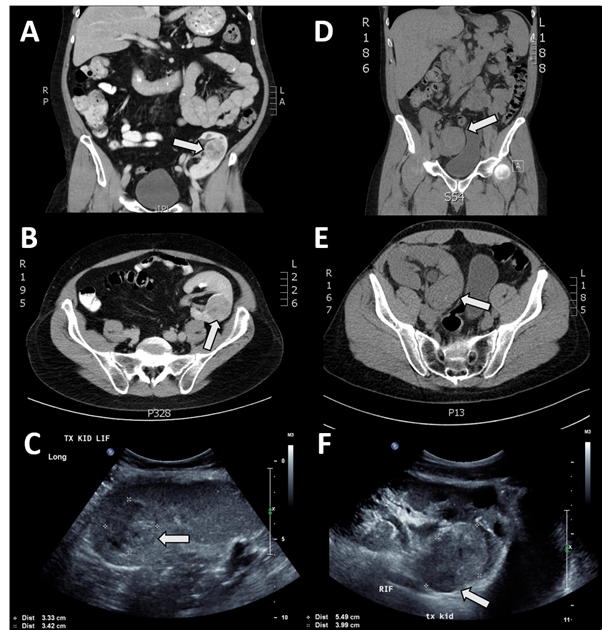

A 55-year-old man underwent graft nephrectomy after a solid mass lesion was detected in his transplanted kidney on ultrasound and confirmed by computed tomographic (CT) scan (Figure 1A-C). The kidney transplant was performed in 1997 following end-stage kidney disease due to focal segmental glomerulosclerosis (18-year functioning graft; estimated glomerular filtration rate [eGFR] prior to surgery was 45 ml/min per 1.73 m2). Immunosuppressive therapeutic regimen prior to surgery included prednisolone (5 mg/day), mycophenolate mofetil (2000 mg/day) and tacrolimus (0.5 mg/day). In the non-neoplastic kidney sections, there were glomerular hypertrophy and focal segmental glomerulosclerosis, with no transplant glomerulopathy. Mild transplant arteriopathy was present, and there was minimal tubular atrophy/interstitial fibrosis (<10% cortex). There was no evidence of rejection. Multiple simple cortical cysts (Figure 2A) and papillary adenomas (<5 mm) were present.

Figure 1

Figure 1. A. Computer tomographic scan (CT) case 1: coronal section showing transplant kidney in left iliac fossa; distinct mass present in upper pole and enhanced with contrast, designated by arrow. B. CT case 1: transverse section showing distinct mass in transplant kidney enhanced with contrast, predominantly posteriorly located. C. Ultrasound case 1: showing distinct mass within kidney. D. CT case 2, coronal section showing transplant kidney in right iliac fossa; indiscriminate mass located in lower pole without contrast enhancement. E. CT case 2, transverse section showing indiscriminate mass in posterior portion of kidney. F. Ultrasound case 2, showing distinct mass in posterior portion of kidney cortex.

A 44-year-old man underwent graft nephrectomy after a solid mass lesion was detected in his transplanted kidney on ultrasound, and confirmed by a CT scan (Figure 1D-F). The transplant was received in 1996 (19-year functioning graft; eGFR prior to surgery was 26 ml/min per 1.73 m2). Histology of the non-neoplastic kidney showed mild parenchymal scarring with some glomerulitis and transplant glomerulopathy present. Moderate transplant arteriopathy and hyaline arteriosclerosis were also present. Indications of active chronic antibody-mediated rejection were present in the microvessels (glomerular and peritubular capillaries) and arteries, as evidenced by C4d immunoperoxidase stain positivity. Multiple cortical cysts were present.